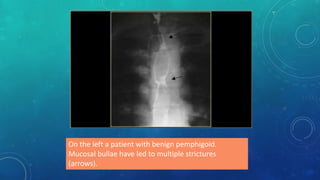

On the left a patient with benign pemphigoid.

Mucosal bullae have led to multiple strictures

(arrows).